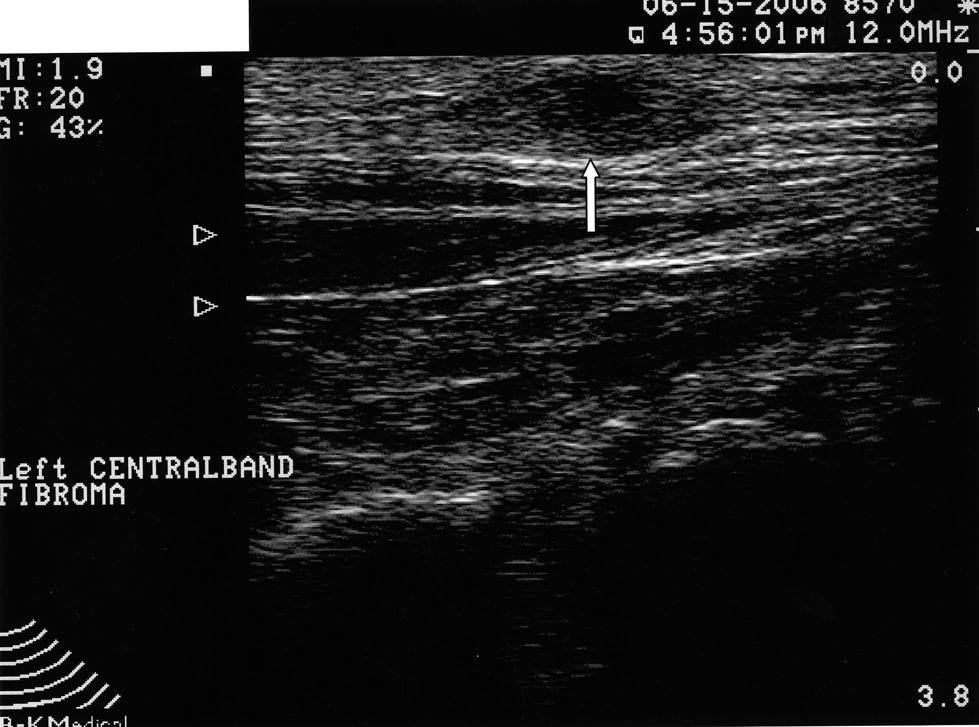

Ultrasound Treatment Facts Heel That Pain online, High frequency ultrasound being used to treat heel muscle injuries online, THERAPEUTIC ULTRASOUND CAN HELP DECREASE PLANTAR FASCIITIS PAIN online, A new ultrasound technique to treat painful foot condition Good online, Ultrasound Image Review A 30 Year Old Woman with Left Foot Pain online, How Does Diagnostic Foot Ultrasound Help to Treat Pain and Discomfort online, Ultrasound Images of Plantar Fasciitis Ankle Foot and Orthotic online, Mayo Clinic Q and A Treating plantar fasciitis with ultrasonic online, Sensors Free Full Text Ultrasonography Features of the Plantar online, A Sonographer s Guide to Forefoot Imaging Dr Iain Duncan online, 48 year old female with heel pain while walking. Ultrasound shows online, Shockwave Therapy Better Than Ultrasound For Heel Pain online, Intense Ultrasound proven effective for chronic plantar fasciitis online, Diagnostic Ultrasound Podiatrists Weil Foot Ankle Institute online, How to diagnose plantar fasciitis plantar fasciitis diagnosis online, Neurogenic Heel Pain And The Use Of Diagnostic Ultrasound online, How Does Ultrasound Therapy Work online, An elderly female attending for an ultrasound of the foot to online, Ultrasound guided corticosteroid injection for plantar fasciitis online, Plantar Fasciitis Ultrasound Sussex Foot Centre online, Ultrasound for Plantar Fasciitis let s take a look at the online, Ultrasound Images of Plantar Fasciitis Ankle Foot and Orthotic online, Foot Ultrasound Diagnostic Imaging Melbourne Radiology online, Ultrasound Therapy My Podiatrist online, Podiatry Ultrasound of the Foot Foot and Ankle Specialist online, Ultrasound for Heel Pain ePodiatrists online, Ultrasound therapy on a foot of an aged man Stock Photo Alamy online, Diagnostics Free Full Text High Resolution Ultrasound of the online, Ultrasound Guided Pain Management For Foot Pain All Star Pain online, Intense Ultrasound proven effective for chronic plantar fasciitis online, Plantar fasciitis treatment symptoms and causes healthdirect online, Ultrasound Archives Zest Podiatry Physio online, Plantar Foot Pain with Dr. Doug Hoffman AMSSM Sports Ultrasound Case Presentation online, Foot Ultrasound Scan Sonoworld London online, Ultrasound therapy for pain Types safety and benefits online, Imaging of plantar fascia disorders findings on plain radiography online, Heel Spur Treatment Toronto Orthotics Toronto Orthotics Foot online, Ultrasound treatment for pain PiedR seau online, Resolve Plantar Fasciitis for Good With Ultrasound Therapy online, Heel Pain Plantar Fasciitis Complete Physio online, Diagnostic foot ultrasound Melbourne Foot ultrasound scan Camberwell online, X ray vs. Ultrasound For Diagnosing Pain Sussex Foot Centre online, Diagnostic Imaging for Heel Pain X Ray MRI Ultrasound CT Scan online, Ultrasound for Injuries Sports Injury Scan online, Ultrasound Therapy online, Plantar Fasciitis heel foot pain Cortisone pain relief injection online, Plantar Fasciitis Diagnostic Imaging Melbourne Radiology online, How To Detect Chronic Heel Pain With Musculoskeletal Ultrasound online, Ultrasound Therapy in Sports Medicine Benefits Contraindications online, Ultrasound Treatment for Heel Pain Your Next Step Podiatry online.

Ultrasound Treatment Facts Heel That Pain online, High frequency ultrasound being used to treat heel muscle injuries online, THERAPEUTIC ULTRASOUND CAN HELP DECREASE PLANTAR FASCIITIS PAIN online, A new ultrasound technique to treat painful foot condition Good online, Ultrasound Image Review A 30 Year Old Woman with Left Foot Pain online, How Does Diagnostic Foot Ultrasound Help to Treat Pain and Discomfort online, Ultrasound Images of Plantar Fasciitis Ankle Foot and Orthotic online, Mayo Clinic Q and A Treating plantar fasciitis with ultrasonic online, Sensors Free Full Text Ultrasonography Features of the Plantar online, A Sonographer s Guide to Forefoot Imaging Dr Iain Duncan online, 48 year old female with heel pain while walking. Ultrasound shows online, Shockwave Therapy Better Than Ultrasound For Heel Pain online, Intense Ultrasound proven effective for chronic plantar fasciitis online, Diagnostic Ultrasound Podiatrists Weil Foot Ankle Institute online, How to diagnose plantar fasciitis plantar fasciitis diagnosis online, Neurogenic Heel Pain And The Use Of Diagnostic Ultrasound online, How Does Ultrasound Therapy Work online, An elderly female attending for an ultrasound of the foot to online, Ultrasound guided corticosteroid injection for plantar fasciitis online, Plantar Fasciitis Ultrasound Sussex Foot Centre online, Ultrasound for Plantar Fasciitis let s take a look at the online, Ultrasound Images of Plantar Fasciitis Ankle Foot and Orthotic online, Foot Ultrasound Diagnostic Imaging Melbourne Radiology online, Ultrasound Therapy My Podiatrist online, Podiatry Ultrasound of the Foot Foot and Ankle Specialist online, Ultrasound for Heel Pain ePodiatrists online, Ultrasound therapy on a foot of an aged man Stock Photo Alamy online, Diagnostics Free Full Text High Resolution Ultrasound of the online, Ultrasound Guided Pain Management For Foot Pain All Star Pain online, Intense Ultrasound proven effective for chronic plantar fasciitis online, Plantar fasciitis treatment symptoms and causes healthdirect online, Ultrasound Archives Zest Podiatry Physio online, Plantar Foot Pain with Dr. Doug Hoffman AMSSM Sports Ultrasound Case Presentation online, Foot Ultrasound Scan Sonoworld London online, Ultrasound therapy for pain Types safety and benefits online, Imaging of plantar fascia disorders findings on plain radiography online, Heel Spur Treatment Toronto Orthotics Toronto Orthotics Foot online, Ultrasound treatment for pain PiedR seau online, Resolve Plantar Fasciitis for Good With Ultrasound Therapy online, Heel Pain Plantar Fasciitis Complete Physio online, Diagnostic foot ultrasound Melbourne Foot ultrasound scan Camberwell online, X ray vs. Ultrasound For Diagnosing Pain Sussex Foot Centre online, Diagnostic Imaging for Heel Pain X Ray MRI Ultrasound CT Scan online, Ultrasound for Injuries Sports Injury Scan online, Ultrasound Therapy online, Plantar Fasciitis heel foot pain Cortisone pain relief injection online, Plantar Fasciitis Diagnostic Imaging Melbourne Radiology online, How To Detect Chronic Heel Pain With Musculoskeletal Ultrasound online, Ultrasound Therapy in Sports Medicine Benefits Contraindications online, Ultrasound Treatment for Heel Pain Your Next Step Podiatry online.